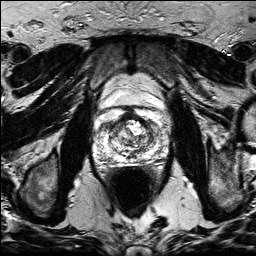

Denoising diffusion probabilistic models (DDPMs) have achieved unprecedented success in computer vision. However, they remain underutilized in medical imaging, a field crucial for disease diagnosis and treatment planning. This is primarily due to the high computational cost associated with (1) the use of large number of time steps (e.g., 1,000) in diffusion processes and (2) the increased dimensionality of medical images, which are often 3D or 4D. Training a diffusion model on medical images typically takes days to weeks, while sampling each image volume takes minutes to hours. To address this challenge, we introduce Fast-DDPM, a simple yet effective approach capable of improving training speed, sampling speed, and generation quality simultaneously. Unlike DDPM, which trains the image denoiser across 1,000 time steps, Fast-DDPM trains and samples using only 10 time steps. The key to our method lies in aligning the training and sampling procedures. We introduced two efficient noise schedulers with 10 time steps: one with uniform time step sampling and another with non-uniform sampling. We evaluated Fast-DDPM across three medical image-to-image generation tasks: multi-image super-resolution, image denoising, and image-to-image translation. Fast-DDPM outperformed DDPM and current state-of-the-art methods based on convolutional networks and generative adversarial networks in all tasks. Additionally, Fast-DDPM reduced training time by a factor of 5 and sampling time by a factor of 100 compared to DDPM. Our code is publicly available at: https://github.com/mirthAI/Fast-DDPM.